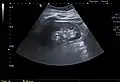

A very small (8 mm) simple renal cyst.

Bosniak II cyst at the lower pole of right kidney with septations within.